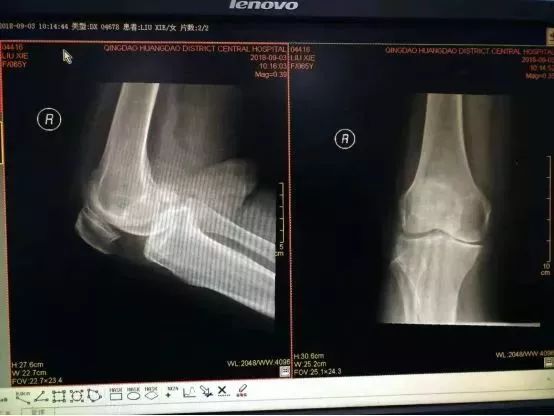

术前右膝关节DR片

术前双下肢全长片